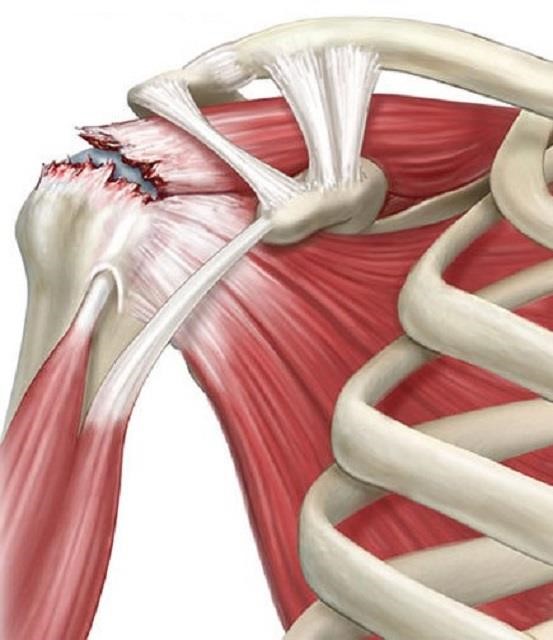

Artroscopia Hombro